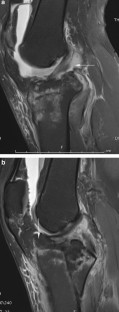

Fig. 1